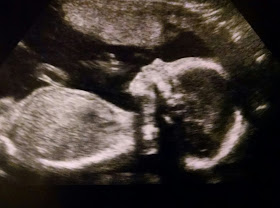

Yup! Going to show off my perfectly healthy, tiny baby boy. I am so relieved and feeling so blessed. He is my little miracle.

His little feet!!!

Side profile

Front of the face.. I know, a little creepy if you are not fully in love.

And a side profile, with his hand by his mouth.

And a side profile with both his hands by his mouth, looking like one very odd, long, many fingered hand.

This is my favorite picture. He is trying to latch onto his hand. When we first started the ultrasound he was sucking his thumb. He lost it and spent the remainder of the ultrasound, about 50 minutes, with both hands up to his face, rooting around trying to suck on them. He needs his thumb!!!

His precious, tiny little foot.

He is indeed small, about 34%. Babies this age weigh over a pound, usually by a few ounces. My little guy is about 13 oz, which will make him a perfect 6ish pounds at birth. All of my kids have been between 6-7 pounds. The Dr said he is perfect, so I am not going to worry. Heaven knows I am giving him enough nutrition. Oink.

He is head down, with his spine up the side of my stomach, and his feet stretched way out, about 2-3 inches above my belly button. He had his legs held straight for a good portion of the ultrasound. He is just chillin' not worrying too much about putting his feet places they don't belong. I am ok with this, as long as he is healthy and happy.